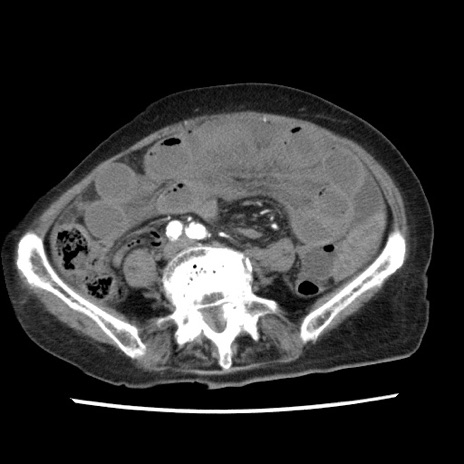

症例1(横断像)

【症例】80歳代女性

【主訴】腹痛

【現病歴】8時間前から腹痛あり来院。

【既往歴】糖尿病、脂質異常症、子宮体癌にて子宮全摘術

【身体所見】意識清明・会話良好だが腹痛で苦悶様、全腹部にわたって反跳痛と圧痛あり

【データ】WBC 13600、CRP 0.14、LDH 224、CK 90